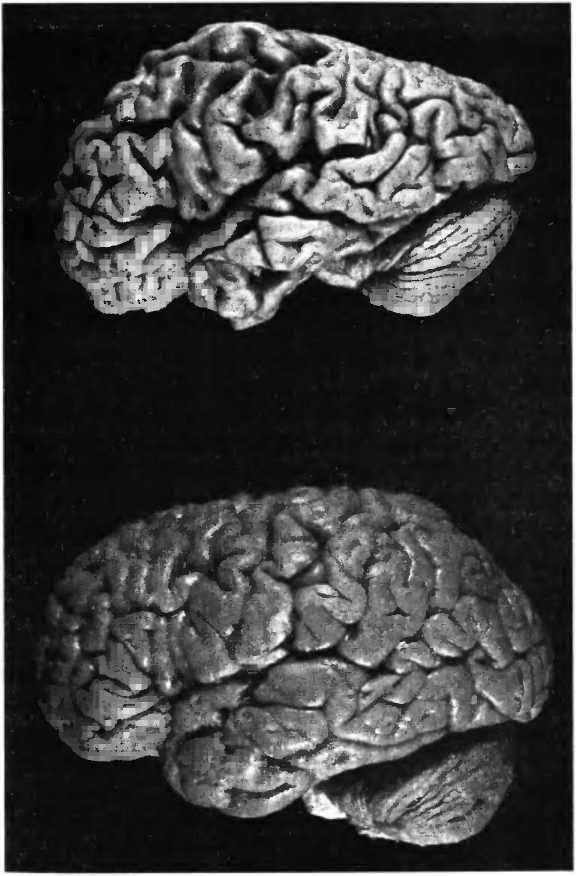

Несмотря на часто сильное сморщивание мозга при болезни Альцгеймера (рис. 31), так что он становится похож на грецкий орех, общее число нейронов в его структуре не уменьшается. Вопреки распространенному мнению, массовой гибели нервных клеток во всем мозге не происходит. Смерть клеток ограничивается пределами нескольких областей мозга: энторинальной коры, части гиппокампа и голубого пятна (locus coeruleus) — и наступает довольно поздно, тогда как снижение активности и поэтому сморщивание нервных клеток (рис. 32) можно наблюдать по всему мозгу уже на ранних стадиях болезни. Этим объясняется тот факт, что в начале болезни ее симптомы могут быть подвержены значительным колебаниям. В какой-то момент у человека могут резко проявиться симптомы деменции, но после этого он вновь оказывается в состоянии поддерживать разговор на обычном уровне. Если бы причиной нарушений памяти на ранней стадии болезни действительно являлась смерть клеток, то никакие колебания симптоматики не возникали бы. Смерть клетки необратима. Еще до того как возникают первые нарушения памяти, измерения показывают уменьшение в мозге глюкозообмена. Внутривенное вливание глюкозы или инсулина улучшает когнитивные способности и указывает на то, что нарушение обмена веществ в мозге является фактором, ограничивающим функциональные способности пациентов.

Иллюстрация к книге — Мы - это наш мозг. От матки до Альцгеймера [i_043.jpg]

Рис. 31. При болезни Альцгеймера часто наблюдается сильное сморщивание (атрофия) мозга, он становится похож на грецкий орех. Внизу — здоровый мозг.